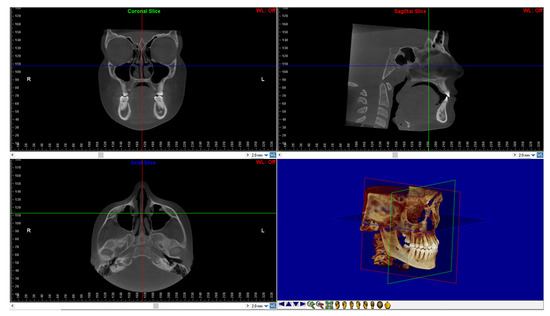

After, DICOM files of all CBCTs were imported into the Dolphin 3D software (Dolphin Imaging1, version 11.0, Chatsworth, CA, USA) to perform the reorientation of the skull according to a validated protocol [24,25] (Figure 1).

Figure 1. Head reorientation in the axial, sagittal, and coronal planes of CBCT scans. The 3D image shows the head orientation in 3D space.